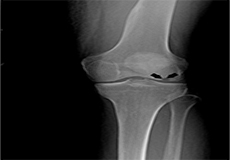

Total Knee Replacement

A Total Knee Replacement (TKR) or Total Knee Arthroplasty is a surgery that replaces an arthritic knee joint with artificial metal or plastic replacement parts called the 'prostheses'.